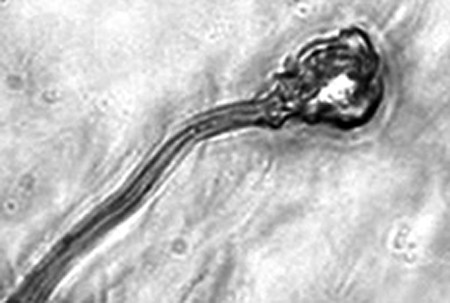

英國培育出人造精子。

顯微鏡下的人造精子。

據報告的主要作者卡里姆教授介紹,這種試管培育精子(IVDsperm)與人類自然產生的精子并不完全一樣,但兩者擁有4個重要的相似點:它們包含有23個染色體;有精子那樣的頭和尾巴;有可以使卵細胞受精的蛋白質;它們也可以像天然精子一樣游動。